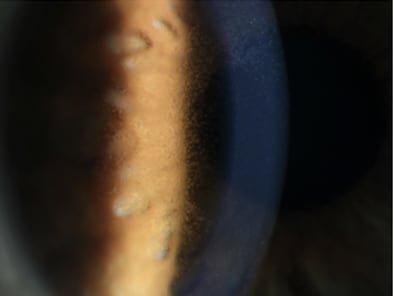

To emphasize the importance of attendees monitoring patients using the medications mentioned, Dr. Canestraro provided real patient examples and how they were handled. OM